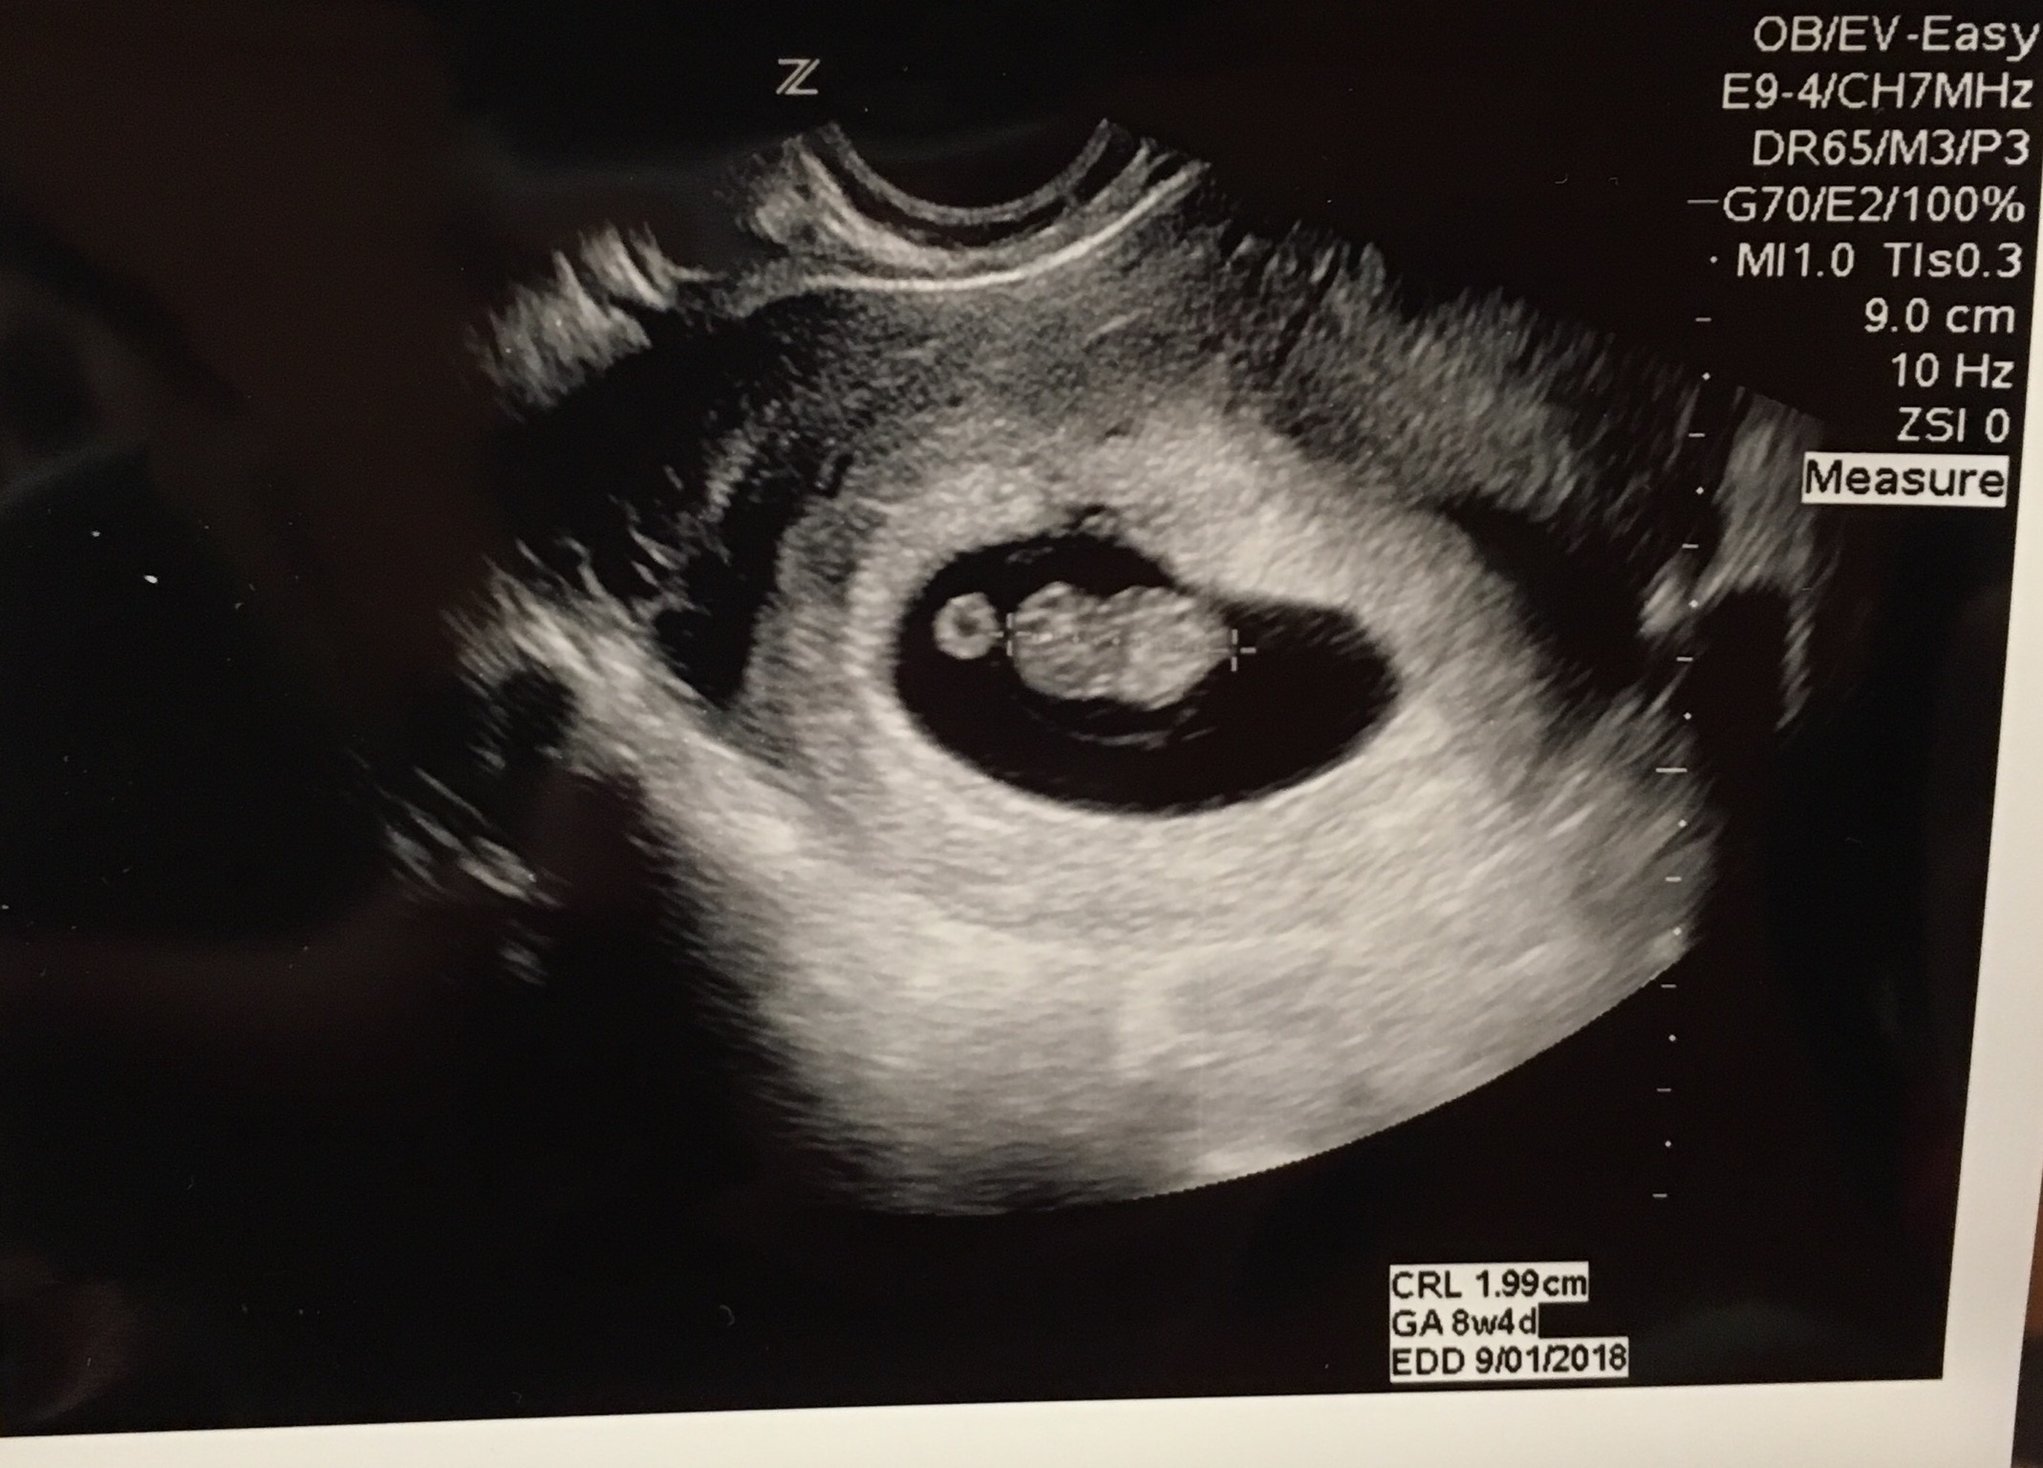

I might be biased, but how cute!!! You can see its little arm buds! I am 7w5d, but the baby measured at 8w1d. Bpm was 171. So far so good! Today was such a happy day!